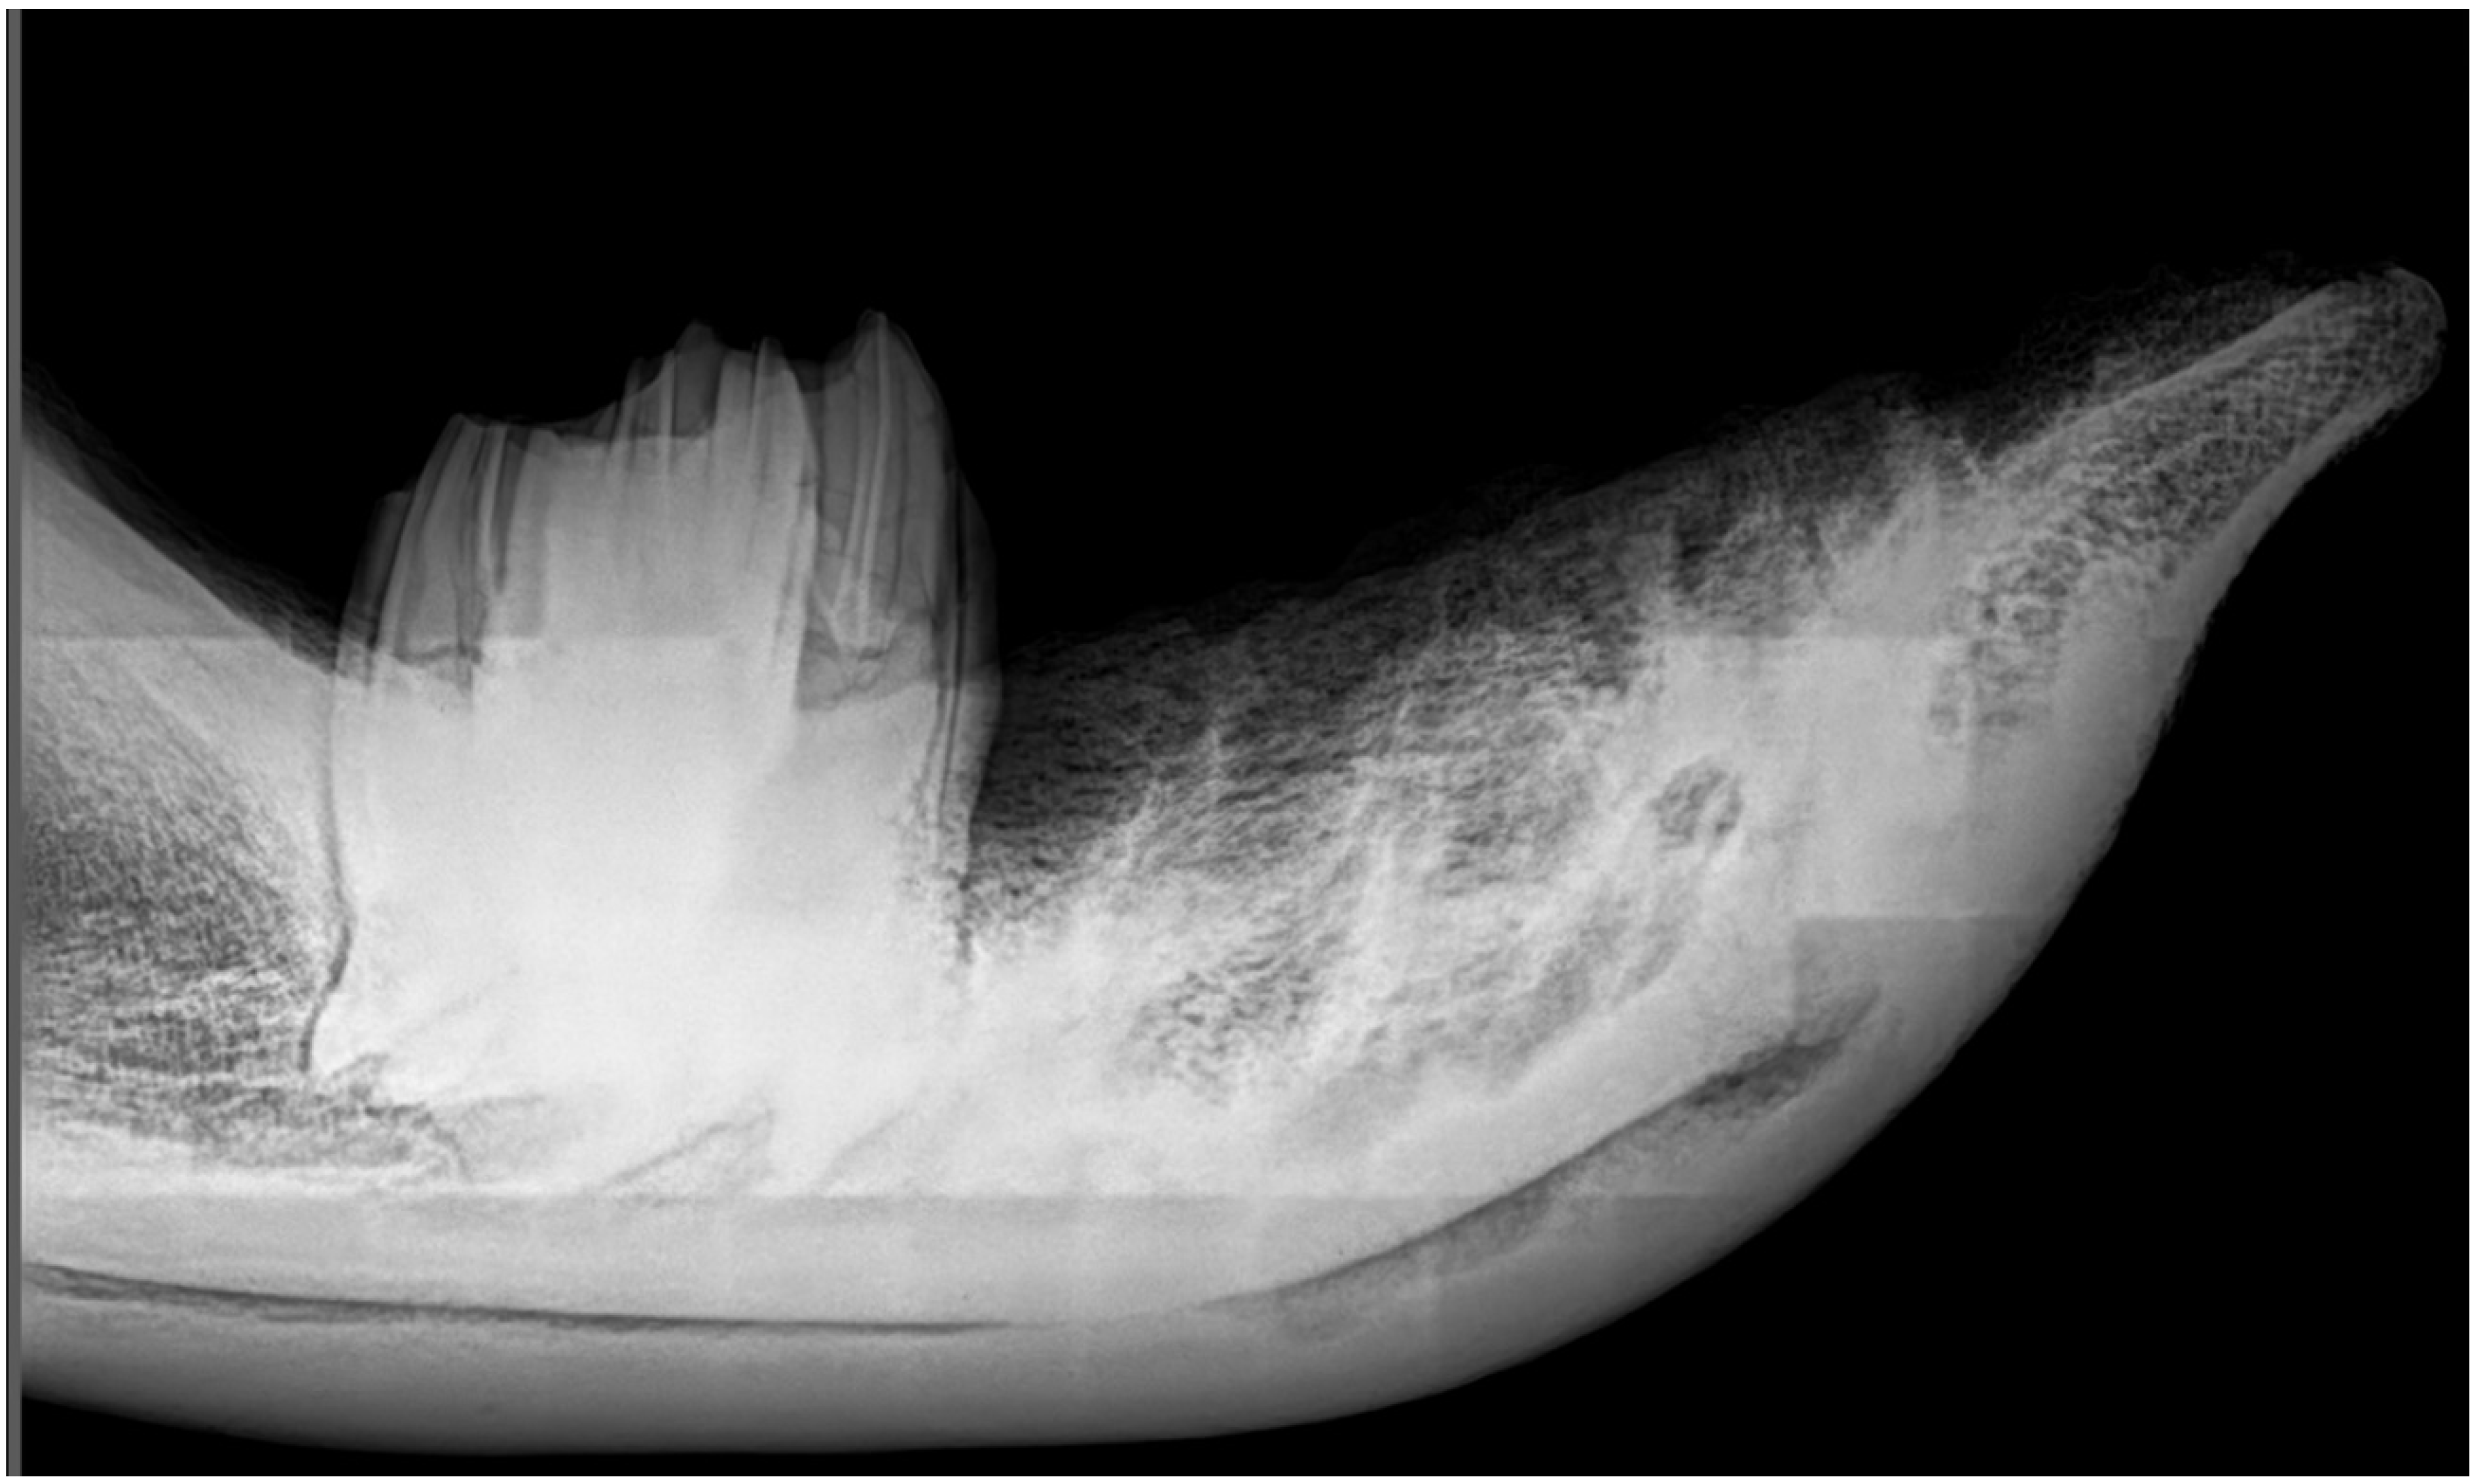

3.3. X-ray Imaging of the Mandible